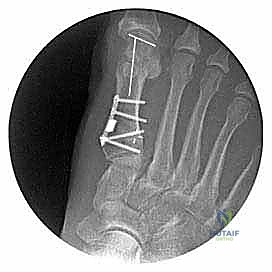

Image

The plate has been set into position by insertion of the first screw.